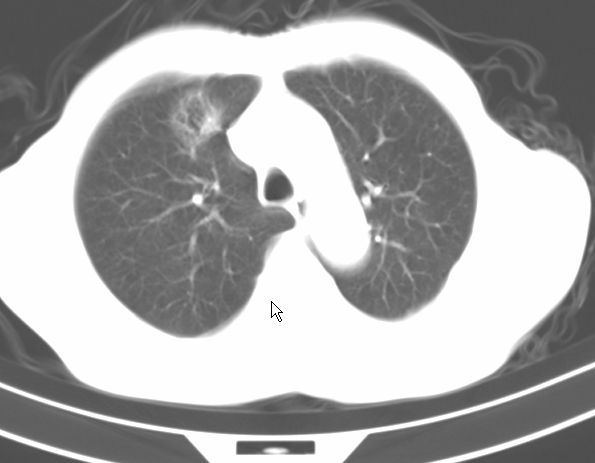

标题: CT17095:胸部病变请大家看看是什么性质的

请大家看看是什么性质的。炎性病变首先考虑哪一种炎症。

支持右肺上叶前段\\下叶内基底段感染,建议抗炎治疗后复查,除外结核.

支持右肺上叶前段\\下叶上段感染,建议抗炎治疗后复查,除外结核.

支持右肺上叶前段、下叶内基底段感染,建议抗炎治疗后复查,除外结核.

右肺上叶前段及下叶内基底段感染性病变;建议抗炎治疗后复查。

楼主说是炎症,凭啥?典型的周围型肺癌(腺癌可能性大),肝内可能已有转移,强化看看吧。